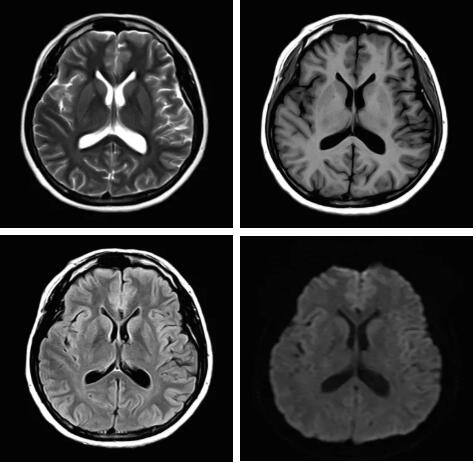

見所未見 微小腫瘤無處遁藏——

“螢火蟲”成像技術(shù) 顱內(nèi)腫瘤微小病灶檢出新發(fā)現(xiàn)

此技術(shù)主要用于神經(jīng)系統(tǒng)惡性腫瘤,以及其他腫瘤腦轉(zhuǎn)移瘤篩查。傳統(tǒng)情況下做腫瘤腦轉(zhuǎn)移篩查,很容易漏掉5mm以下小病灶,臨床發(fā)現(xiàn)后干預(yù)治療比較晚,要實現(xiàn)2mm高空間分辨率和超薄層全腦掃描在保證信噪比的情況下需要很長時間大概十多分鐘,而且薄層增強序列顱內(nèi)血管呈高亮信號,會干擾顱內(nèi)小病灶的觀察,血管和小病灶區(qū)分困難。佳能”螢火蟲”成像技術(shù)既可以實現(xiàn)高空間分辨率和超薄層(最薄可實現(xiàn)0.2mm)全腦掃描,掃描時間短,2-3分鐘即可實現(xiàn)全腦3D掃描,同時避免了血管高亮信號的干擾,對顱內(nèi)原發(fā)或繼發(fā)的微小腫瘤檢查有重大意義。“螢火蟲”成像技術(shù)具有磁敏感效應(yīng),對于亞急性血敏感敏感,可以區(qū)分出血和強化的腫瘤。